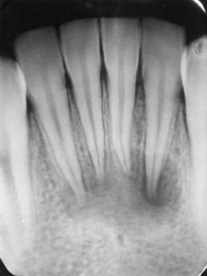

Although the root canal system is complex and completely disinfecting it is challenging, endodontic treatments have high success rates ranging between 85% and 95% (7). Endodontic treatment has the highest success rates when the pulp is vital. This is attributed to the presence of microorganisms in the pulp chamber only (7). However, failure can be attributed to the recontamination of the root canal system or the persistence of the infection, especially in the periradicular area, which leads to root and bone resorption (7). The success rate of endodontic treatment can be influenced by the presence of a hermetic seal, the absence of spontaneous and provoked painful symptoms, repair of periodontal tissue, and restoration of function (7). The most prevalent reason for the failure of endodontic treatment is the reinfection or persistence of infection due to a lack of a coronal seal (8, 9). Therefore, endodontic treatment clinical and radiographic follow-up is mandatory to ensure longevity of the treatment (Figures 1 and 2) (10). The European Society of Endodontics recommends taking a follow-up radiograph after one year, and in case of a periapical lesion, radiographs should be taken two to four years post-operative (11, 12).

Figure 1: A radiographic image of lower incisors with large periapical lesions (13).

Figure 2: A radiographic image of a 3-month follow-up post-endodontic treatment depicting healing of the periapical lesions (13).